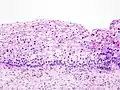

Grad III CIN.

- CIN III: (hochgradige Dysplasie) durchzieht fast das gesamte Epithel (Carcinoma in situ).

Die CIN III gilt als sogenannte obligate Präkanzerose, das heißt, dass ein Übergang zum Zervixkarzinom sehr wahrscheinlich ist.

Das Durchschnittsalter der Patientinnen beim Auftreten einer CIN I und CIN II beträgt 24–27 Jahre. Etwa die Hälfte der CIN-1-Läsionen bilden sich zurück. Rund 10 % schreiten bis zum CIN III voran und 2 % werden zu einem invasiven Cervixkarzinom. Die Prognose ist in einem hohen Maß abhängig vom Virustyp. Während Dysplasien durch Infektionen mit sogenannten low-risk Papillomviren sich meist spontan zurückbilden, führen sogenannte high-risk Papillomviren häufig zu einer CIN III und, wenn sie nicht behandelt werden, zu einem Zervixkarzinom. Das Durchschnittsalter der Patientinnen bei der Entdeckung einer Läsion der Stufe CIN III rangiert zwischen 35 und 40 Jahren.[1]